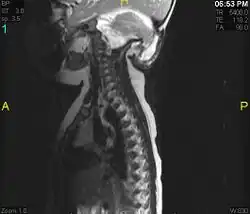

Diagnosis is made through a combination of patient history, neurological examination, and medical imaging.[14] Magnetic resonance imaging (MRI) is considered the preferred imaging modality for Chiari malformation.[15] The MRI visualizes neural tissue such as the cerebellar tonsils and spinal cord as well as bone and other soft tissues. CT and CT myelography are other options and were used prior to the advent of MRI, unfortunately the resolution of CT based modalities do not characterize syringomyelia and other neural abnormalities as well.

By convention, the cerebellar tonsil position is measured relative to the basion-opisthion line, using sagittal T1 MRI images or sagittal CT images.[16] The selected cutoff distance for abnormal tonsil position is somewhat arbitrary, as not every person will be symptomatic at a certain amount of tonsil displacement, and the probability of symptoms and syrinx increases with greater displacement; however, greater than 5 mm is the most frequently cited cutoff number, though some consider 3–5 mm to be "borderline,"; pathological signs and syrinx may occur beyond that distance.[16][17][18] One study showed little difference in cerebellar tonsil position between standard recumbent MRI and upright MRI for patients without a history of whiplash injury.[13] Neuroradiological investigation is used to first rule out any intracranial condition that could be responsible for tonsillar herniation. Neuroradiological diagnostics evaluate the severity of crowding of the neural structures within the posterior cranial fossa and their pressure against the foramen magnum. Chiari 1.5 is a term used when both brainstem and tonsillar herniation through the foramen magnum are present.[19]